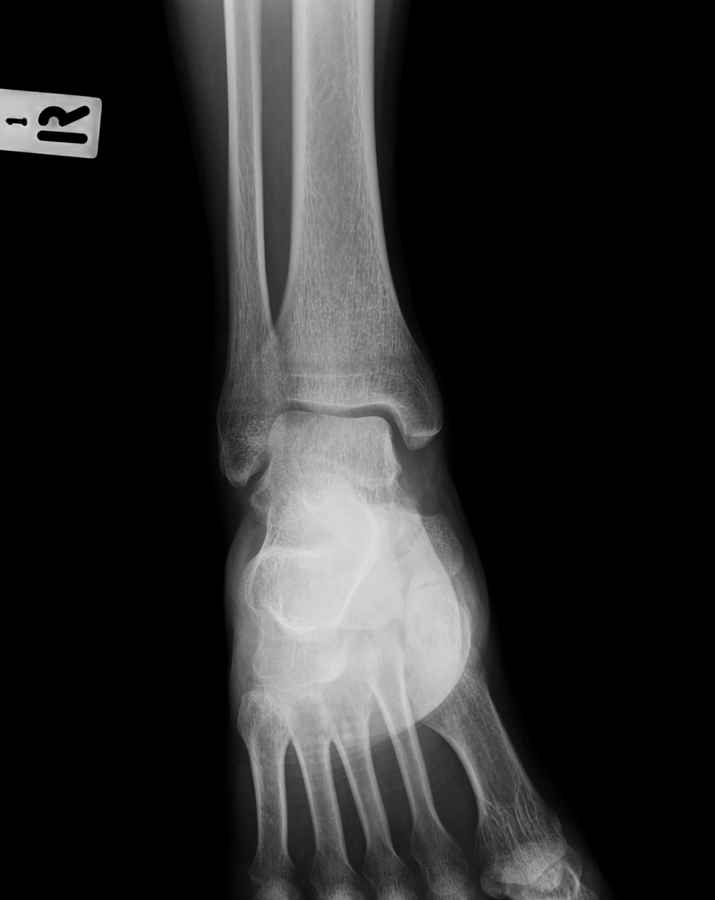

Мужчина 36 лет, пострадал около 8 месяцев назад в ДТП (водитель мотоцикла).

Подтаранный вывих лечили гипсовой лонгетой. Недиагностированным остался перелом ладьевидной кости, который беспокоит в настоящее время. Аваскулярный некроз кости, похоже.